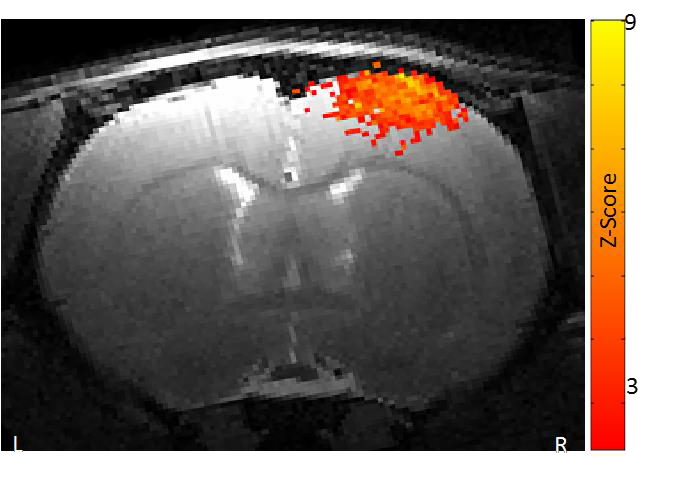

2、功能磁共振成像

功能磁共振成像需要最強(qiáng)的磁場,最好的梯度和最穩(wěn)定的系統(tǒng)。布魯克優(yōu)異的梯度系統(tǒng)確保在單次激發(fā)下得到整個腦部的圖像。功能卓越的勻場單元最大程度地消除平面回波成像幾何形變。特有的頻率和相位穩(wěn)定性保證多次激發(fā)EPI擴(kuò)散張量成像的品質(zhì)。高分辨率的功能磁共振成像可以深入洞察大腦的功能反應(yīng)。

小鼠腦部的功能磁共振成像: